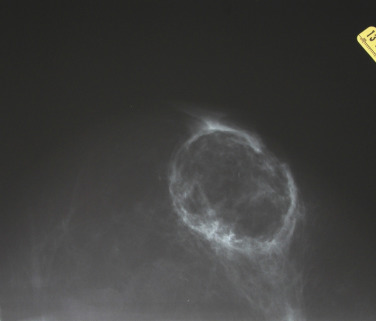

Fat necrosis is another potential complication associated with oncoplastic surgery and more problematic in women with mild to moderate hypertrophy associated with a moderate volume partial mastectomy ( Fig. 17.4 ). Parenchymal rearrangement can be pushed to the limits of vascularity and result in less perfusion to the parenchymal flap, resulting in fat necrosis. When palpable, options include ultrasound and fine needle aspiration for diagnosis and either observation or surgical excision. When extensive, additional rearrangement may not be an option, and a local flap such as a latissimus dorsi may be necessary.